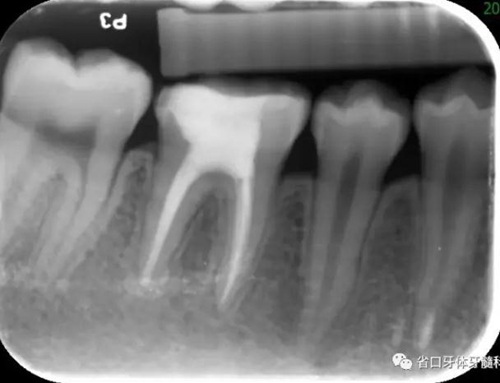

圖4 根管治療術(shù)后17個(gè)月:根分叉和根尖低密度影基本消失

2.本病例為牙髓組織來(lái)源引起齦緣、根分叉至根尖周區(qū)域貫通性的牙周組織損傷,在本病例的治療中,主要針對(duì)牙髓疾患行根管治療,牙周治療僅在初次治療時(shí)行牙周的簡(jiǎn)單處理,結(jié)果表明:完善的根管治療即獲得了良好的牙髓炎癥控制與牙周組織的愈合。

3.治療體會(huì):對(duì)于牙髓牙周聯(lián)合病變的患牙,病因的判斷對(duì)預(yù)后至關(guān)重要。本病例46齲源性的牙髓感染為首發(fā)因素,牙周組織破壞為繼發(fā)損害(圖10 左:Primary Endodontic Lesions with Secondary Periodontal Involvement),有學(xué)者稱之為牙髓牙周聯(lián)合病變,預(yù)后相對(duì)較好;牙周感染繼發(fā)牙髓病變(圖10 中:Primary Periodontal Lesions with Secondary Endodontic Involvement)則稱為牙周牙髓聯(lián)合病變和真性牙周牙髓聯(lián)合病變(圖10 右:True Combined Lesions )預(yù)后相對(duì)差一些。此外,患者的年齡也會(huì)對(duì)預(yù)后產(chǎn)生較大的影響,年齡越輕,其組織修復(fù)與愈合能力越強(qiáng)。